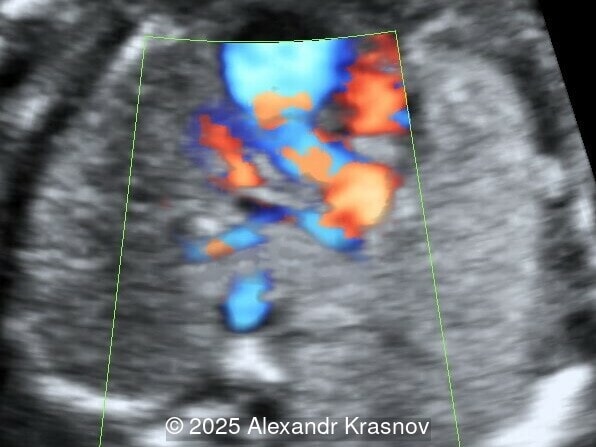

We present a case of total anomalous pulmonary venous return (TAPVR), supracardiac type.

Our ultrasound showed biometry data corresponding to 21 weeks of gestation. During echocardiography, an abnormal drainage of the pulmonary veins was detected in which the pulmonary veins drain into a venous collector linked to the superior vena cava. The four-chamber view and the three-vessel view were altered and raised suspicion of a pathology. The grayscale and color Doppler images of the four-chamber view indicate a smooth posterior wall of the left atrium, increased distance between the left atrium and the descending aorta and the absence of pulmonary veins entering the left atrium (Image 1, 2; Video 1, 2). In the three-vessel view, the diameter of the superior vena cava appears larger than that of the aorta (Image 3, Video 3). In the images of the venae cava, a significant difference is seen between the diameters of the inferior and superior vena cava with significant enlargement of the superior vena cava (Image 4, Video 4). Additionally, there is a pulmonary venous confluent chamber (“twig sign”) behind the left atrium (Image and Video 5). A vertical ascending vein connects the confluent chamber with the superior vena cava where it drains blood from the pulmonary veins (Images 6, 7; Video 6).